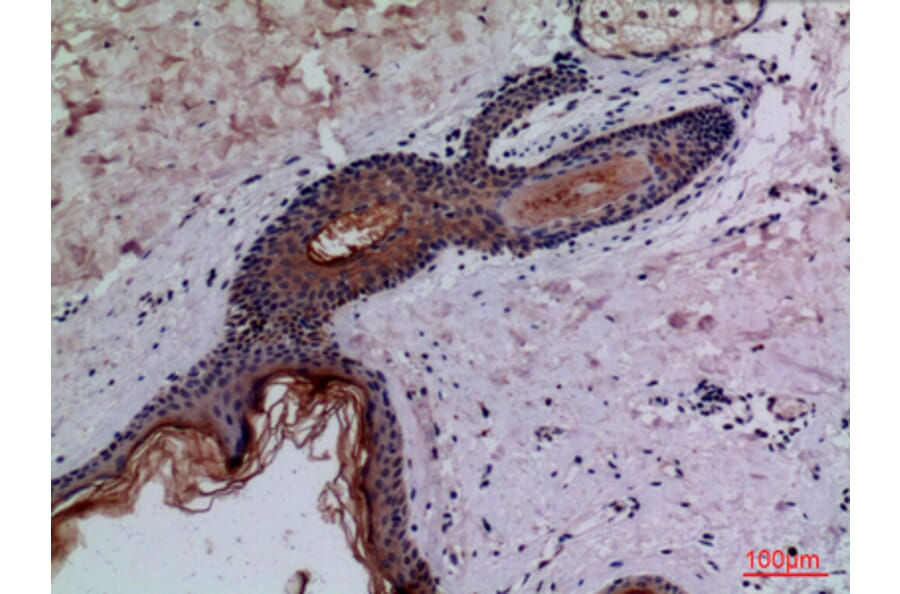

Results: Mice of the Ang-II+01BSUR-group showed a lower aortic-diameter compared to mice of the Ang-II-group and control mice (p < 0.05). Using the elastin-specific-probe, a significant decrease in elastin-destruction was observed in mice of the Ang-II+01BSUR-group. In vivo MR-measurements correlated well with histopathology (y = 0.34x-13.81, R2 = 0.84, p < 0.05), ICP-MS (y = 0.02x+2.39; R2 = 0.81, p < 0.05) and LA-ICP-MS. Immunofluorescence and western-blotting confirmed a reduced IL-1ß-expression.